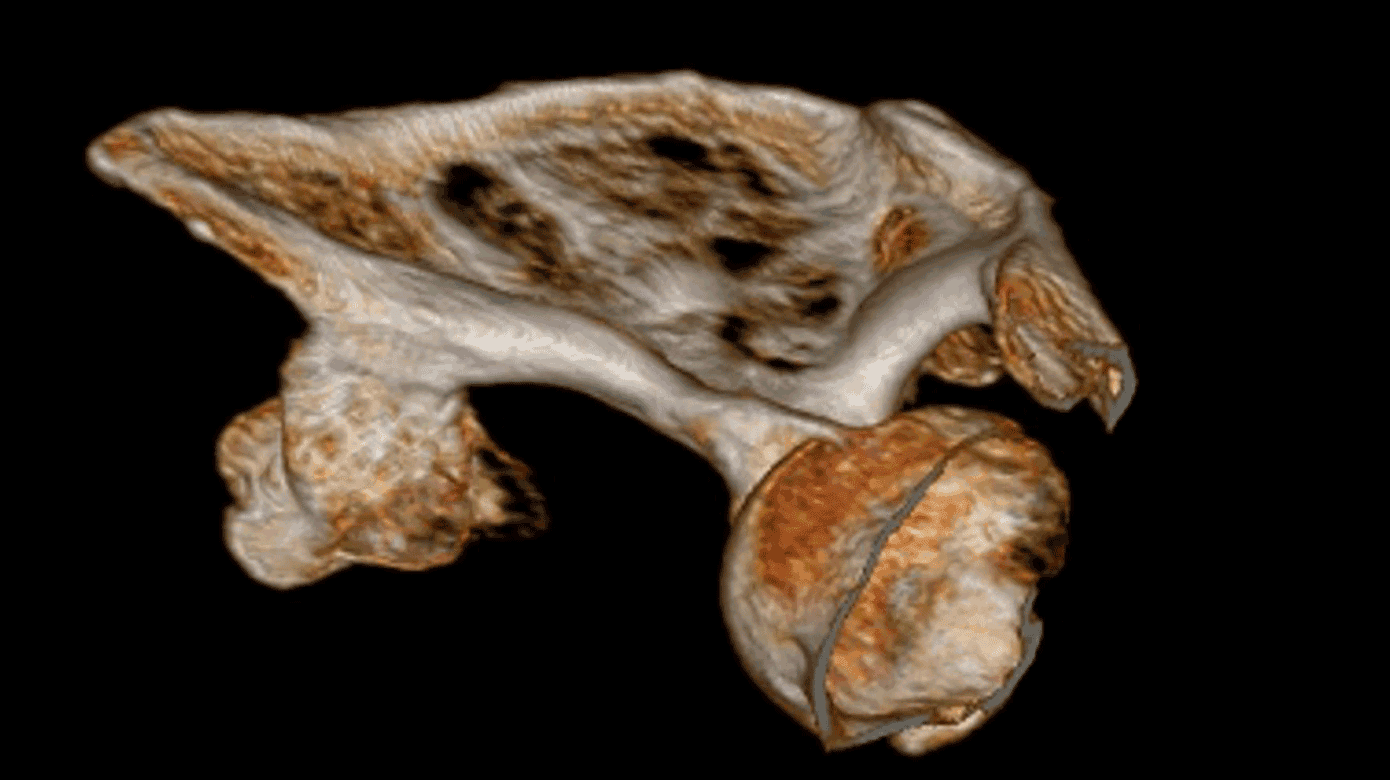

På trods af benigne eksostoser er det essentielt, at patienter med HME følges med ambulante kontroller. Børn med HME følges på højtspecialiserede ortopædkirurgiske afdelinger på Rigshospitalet og Aarhus Universitetshospital. Det primære fokus er diagnostik, herunder genetisk udredning, samt behandling af symptomgivende eksostoser. I voksenalderen er det kontroller, der har til formål at udelukke malign degeneration. I henhold til den nationale retningslinje [16] bør patienter med HME få foretaget en sygdomsstatus med konventionel røntgenundersøgelse, når de er udvokset. Ved osteokondromer på pelvis, columna eller thorax inklusive scapula anbefales supplering med MR-skanning eller CT (Figur 1). Patienter med osteokondromer i truncusområdet, på proksimale humerus eller på proksimale femur tilbydes screening med MR-skanning hvert andet år, som foretages på et sarkomcenter. Perifere eksostoser kontrolleres til klinisk kontrol eller af patienten selv. Klinisk mistanke om malignitet hos voksne opstår, hvis bruskkappen er mere end 2 cm målt på MR-skanning ved eksostosevækst, ved nytilkomne smerter eller ved røntgenundersøgelse af uregelmæssigheder på knoglen [16]. Hos børn er bruskkappen tykkere og anvendes derfor ikke diagnostisk i samme grad [1]. Den estimerede risiko for malign transformation er 2-3,7% hos patienter med HME [17]. Risikoen er 1,5-2 gange højere ved EXT1-mutationer sammenlignet med EXT2-mutationer [18].